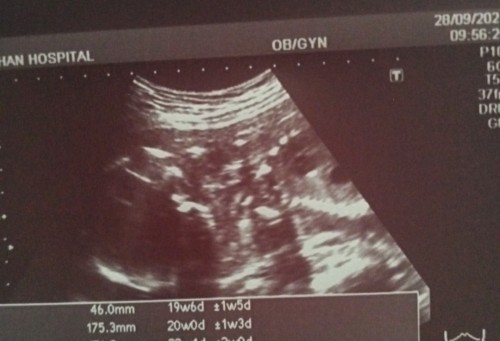

ซาวด์ 4 มิติ ตอน19 W 6Dค่ะ ล่าสุดเมื่อ2วันที่ผ่านมาค่ะ หมอบอกได้ลูกสาวค่ะ